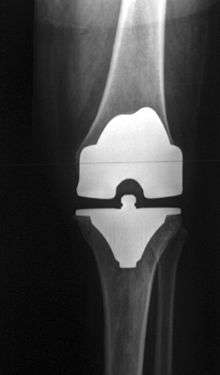

Total knee replacement hardware, including femoral head, tibial plate, patellar plate, and meniscus replacement plate.

A round ended implant is used for the femur, mimicking the natural shape of the joint. On the tibia the component is flat, although it sometimes has a stem which goes down inside the bone for further stability. A flattened or slightly dished high density polyethylene surface is then inserted onto the tibial component so that the weight is transferred metal to plastic not metal to metal. During the operation any deformities must be corrected, and the ligaments balanced so that the knee has a good range of movement and is stable and aligned. In some cases the articular surface of the patella is also removed and replaced by a polyethylene button cemented to the posterior surface of the patella. In other cases, the patella is replaced unaltered.